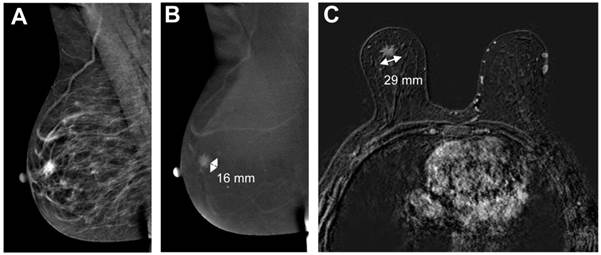

In Figure 4 and 5, examples of good and poor agreement between tumor diameter measurement between CESM and breast MRI can be appreciated.

Figure 5

Example of poor agreement between CESM and breast MRI. The low-energy CESM image (A) shows an ill-defined mass behind the nipple, enhancing on the recombined images (B, 16 mm). Breast MRI showed a spiculated mass (C, 29 mm). Histopathological results showed a 21 mm invasive lobular carcinoma.